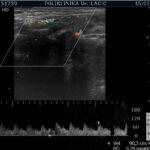

Color Doppler je temeljen na ultrazvučnoj tehnologiji koja pomoću Doppler-ovog efekta procjenjuje prokrvljenost cijele štitnjače i čvorova u štitnjači, kao i limfnih čvorova vrata. Pomoću color Dopplera računamo brzine protoka kroz krvne žile koje hrane štitnjaču, čime dobivamo važne hemodinamske parametre. Na temelju ovih pokazatelja donosimo važne dijagnostičke zaključke, te efikasno pratimo efekte liječenja štitnjače.

U sklopu Centra za štitnjaču Poliklinike Lacić nabavljen je najnoviji američki ultrazvučni aparat sa color Dopplerom Philips Affiniti 70, koji je opremljen jedinstvenim „PureWave“ ultrazvučnim sondama. Tehnologija izrade tzv. „single crystal“ ili „PureWave“ ultrazvučnih sondi omogućuje duboku penetraciju što omogućuje bolju vizualizaciju štitnjače i svih struktura vrata. Philips Affiniti 70 ultrazvučni sustav je jedini sustav u klasi koji može koristiti „single crystal“ ili „PureWave“ tehnologiju. Čisti, uniformni „PureWave“ kristali imaju 85% bolju učinkovitost prilikom emitiranja i primanja ultrazvučnih zraka nego klasični piezoelektrični materijali. Ova izuzetna tehnologija omogućuje naprednu penetraciju uz izvrsnu rezoluciju u dubljim dijelovima slike, čime se postiže vrhunski prikaz štitnjače i svih struktura vrata. Time se omogućuje još točnije mjerenje svih morfoloških kao i hemodinamskih parametara. Na taj način smo u mogućnosti još ranije otkrivati bolesti štitnjače a samim time ih onda i bolje liječiti.